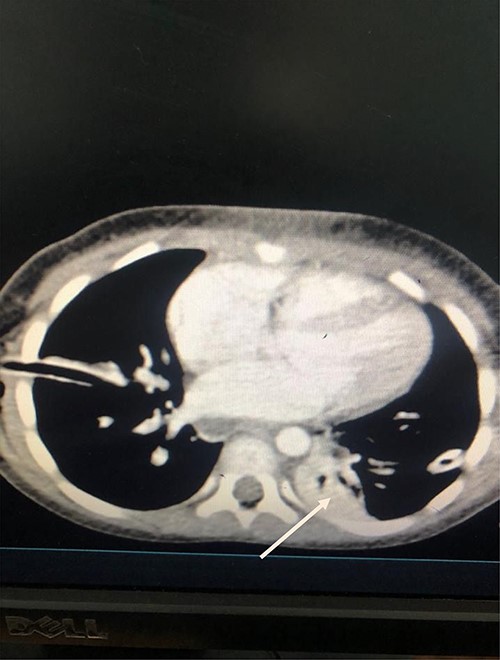

She was kept on conservative management with lipid restriction and octreotide. A day later, she had resolved respiratory signs and symptoms. Control computed tomography (CT) revealed significant improvements with minimal fluid on the left side (Fig. 3).

Axial Slice of the thorax showing bilateral thoracostomy tubes and minimal fluid on the left side (white arrow).